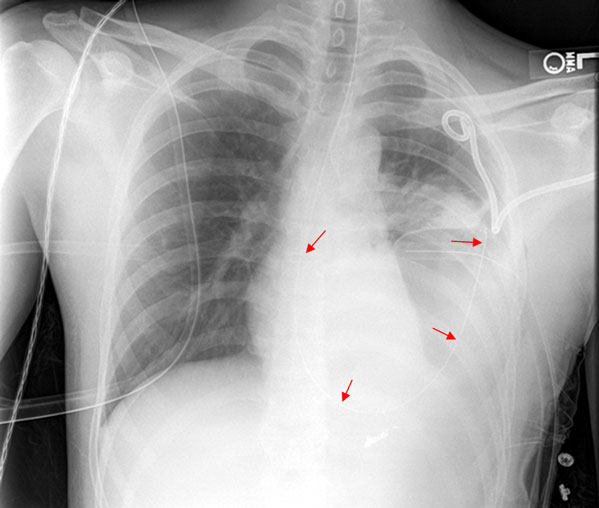

Hemothorax

Hemothorax, an accumulation of blood outside the visceral lung pleura, is a differential diagnosis of decreased breath sounds along with pneumothorax. However, it is differentiated by the presence of dullness to percussion on physical exam.

The management of hemothorax is often non-emergent, as parenchymal lung bleeding is often self-limiting. Initial management is a chest tube (tube thoracostomy).

Either a massive immediate drainage (greater than 1.5 L) or large ongoing drainage of the chest tube (200 to 300 ml per hour) warrants surgical intervention with thoracotomy to ligate the vessel. Bleeding in this manner is known to be thoracic (e.g. intercostal artery), as opposed to pulmonary parenchymal.